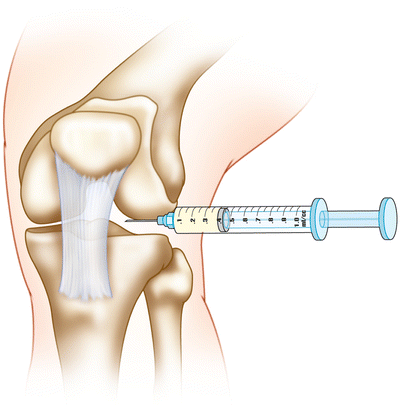

– تزریق مواد ضد التهاب و ترمیم کننده به داخل مفصل زانو

تزریق کورتون به زانو

تزریق کورتون داخل زانو به کاهش التهاب موضعی و بهبود علائم استئوآرتریت زانو کمک می کند. به طور کلی پاسخ به آن، مانند کاهش درد زانو سریع است اما ممکن است در طولانی مدت پایدار نباشد.

تزریق کورتون به زانو اغلب برای درمان علائم حاد و یا شدید استفاده می شود.

در صورت وجود مایع بیش از حد داخل مفصل زانو یا همان آب آوردن زانو، تخلیه آن لازم هست تا از رقیق شدن دارو جلوگیری شود.

تزریق کورتون داخل زانو با رعایت شرایط استریل و در چند دقیقه انجام می گیرد، با تکنیک مناسب و استفاده از داروی بی حسی انجام آن درد زیادی ندارد. از آنجا که کورتیکواستروئید مستقیماً داخل مفصل زانو تزریق می شود، میزان اثرات سیستمیک به حداقل می رسد.

تزریق کورتون داخل زانو دو یا سه بار در سال با فاصله 3 تا 4 ماه قابل انجام هست.

مراقبت های بعد از تزریق شامل 5 تا 10 دقیقه استفاده از یخ موضعی هست و به بیماران توصیه می شود تا 24 تا 48 ساعت پس از تزریق از ایستادن و راه رفتن طولانی خودداری کنند.

تزریق ژل به زانو

مفصل سالم زانو حاوی حدود 4 میلیلیتر مایع مفصلی است که هیالورونیک اسید جزو اصلی این مایع محسوب میشود. این مایع اصطکاک مفصل را کاهش میدهد و مانند بالشتک از زانو، بهخصوص هنگام فعالیت هایی که وزن تحمل میشود، محافظت میکند.

ژل هیالورونیک اسید بصورت دارو با نام های تجاری و وزن مولکولی مختلف ساخته شده است و برای تزریق داخل مفصلی در دسترس می باشد، برتری انواع آن نسبت به همدیگر کاملا مشخص نشده است.

سازمان غذا و داروی آمریکا (FDA) تزریق ژل هیالورونیک اسید را برای مفصل زانو تایید کرده است.

دلیل استفاده از ژل هیالورونیک اسید، انتقال خصوصیات محافظ به مایع سینوویال طبیعی مفصل از جمله جذب فشار، روانکاری مفصل و کاهش اصطکاک سطح غضروف مفصلی هست. هدف از تزریق ژل داخل زانو بهبود عملکرد و کاهش درد زانو می باشد.

در مقایسه با تزریق کورتون داخل زانو به نظر می رسد که اثر تزریق ژل به داخل زانو دیرتر اما با دوام تر هست. هیچ مدرکی وجود ندارد که نشان دهد تزریق ژل هیالورونیک اسید در انسان روند های بیولوژیکی یا پیشرفت آسیب غضروف را در آرتروز زانو تغییر می دهد.

تزریق ژل داخل مفصل زانو و مراقبت های بعد از آن مانند تزریق کورتون داخل مفصل زانو می باشد.

تزریق پی آر پی به زانو

پی آر پی (PRP) همان پلاسمای غنی از پلاک هست که تزریق آن داخل زانو موجب بهبود علایم آرتروز زانو چند ماه بعد از تزریق می شود. تزریق پلاکت موجب کاهش درد زانو و خشکی مفصل و بهبود کیفیت زندگی بیمار می شود. به طور کلی تزریق پلاکت به زانو برای آرتروز زانو روشی ایمن هست و اثرات طولانی تری دارد.

محلول پی آر پی پس از خون گیری(حدود 30 میلی لیتر) از بیمار و سانتریفیوژ کردن آن آماده تزریق می شود. کل زمان لازم برای تزریق پلاک حدود یک ساعت هست ولی روش تزریق پلاکت به داخل زانو و مراقبت های بعد از آن مانند تزریق کورتون و ژل می باشد.